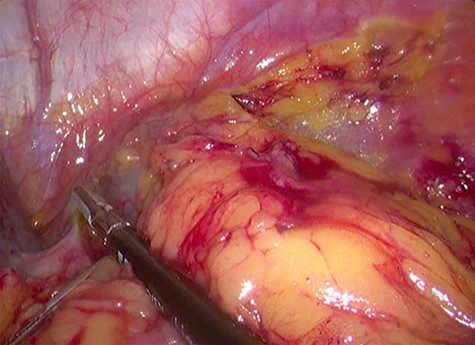

Because of its relatively large size and the patient’s request, he underwent a laparoscopic transperitoneal left adrenalectomy in the right lateral decubitus position (two 10-mm and one 5-mm ports). Intraoperatively, an enlarged left adrenal gland and a cystic lesion closely adherent to it were found, surrounded by adipose tissue (Figs 3 and 4). They were completely resected en bloc and removed in the endobag. No adverse events occurred postoperatively and he was discharged on Day 3.

Laparoscopic en bloc resection of the retroperitoneal cystic lesion adherent to the left adrenal gland and adipose tissue.